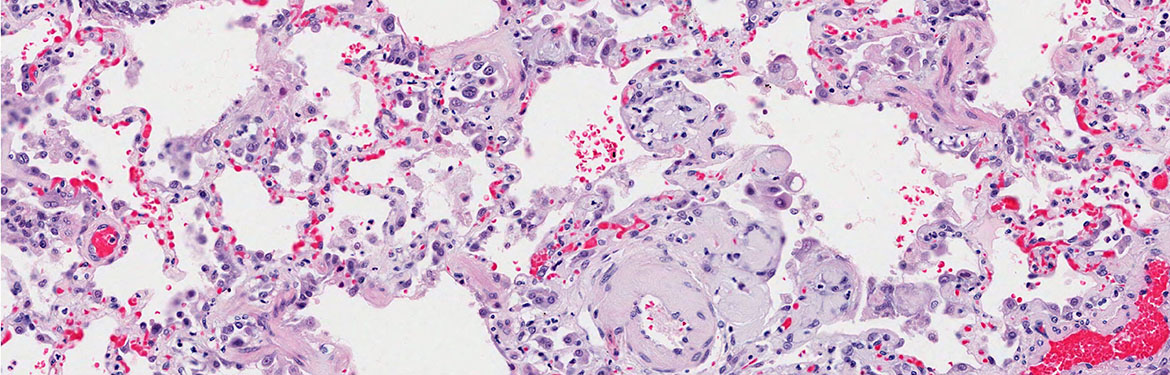

In England we offer breast screening every three years to women aged 50 to 70 years. In 2018/19 the NHS breast cancer screening programme screened over two million women. A potential abnormality was identified in nearly 85,000, who were recalled for further tests. Cancer is detected in nearly 20,000 of these women but a small proportion have types of abnormality that are not cancer. These are called atypical epithelial proliferations, or atypia. Whilst these women do not have cancer, some of them may be 4 times more likely to develop cancer in the future than women without atypia. However, we currently do not know what the true risk is for these women. We do not know how many of these women will develop cancer, or how long it will take and the types of cancer if it does develop. Because of this uncertainty there are no national guidelines and therefore variation in care across the UK. Some screening centres offer women with atypia, regardless of type, mammography tests, every year for 5 years. Other centres continue to offer routine 3-yearly mammograms. We do not know what is the best care for women, as mammography, and the test offered, can also cause discomfort and anxiety.

We also want to investigate to what degree this information differs depending on the type of atypia.